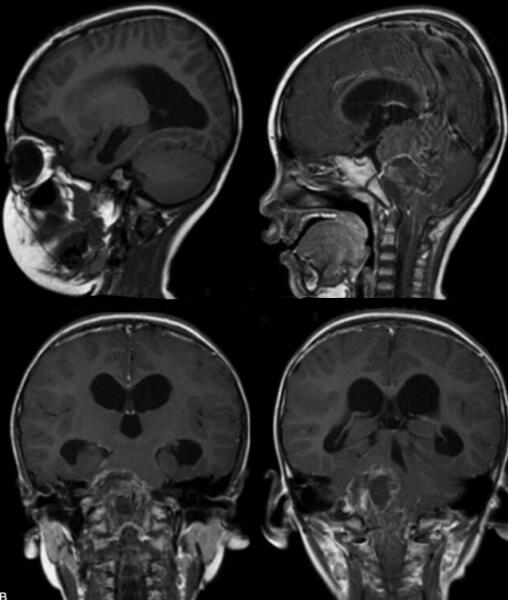

室管膜母细胞瘤(图2)

图2 瘤细胞小、一致,弥漫排列,局部见菊形团排列,见坏死。免疫组化:GFAP(+),Syn(-),NSE(-),EMA(-)